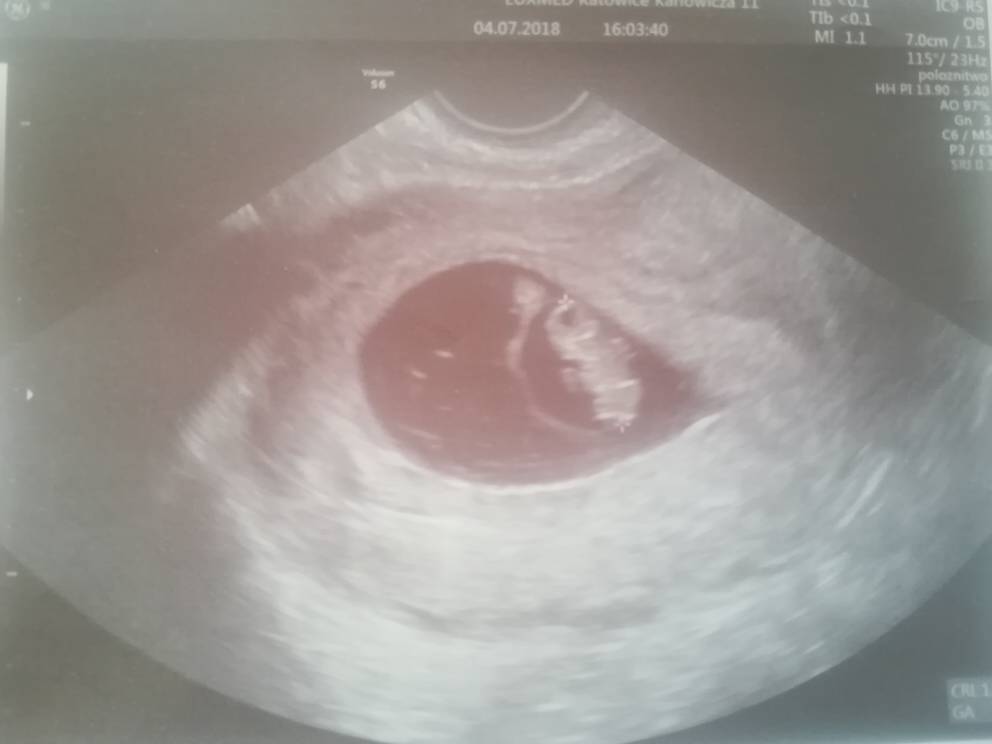

Byłam dzisiaj na wizycie. Bobo ma 1,5 cm i widać było rączki i nóżki :D

IMG_20180704_205441.jpg